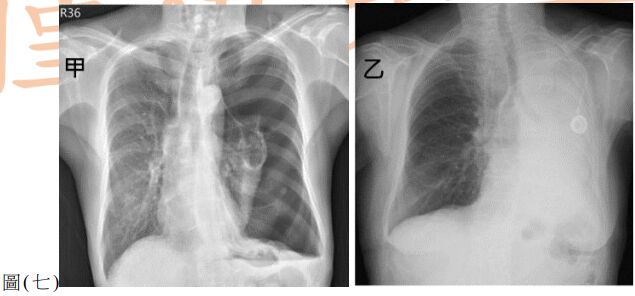

38. 甲、乙兩位病人因呼吸喘促求診,胸部 X 光如圖 ( 七 )。對於是否置放胸管引流改善呼吸 喘促的決策,下列何者正確?

(A) 只有甲適合插胸管 (B) 只有乙適合插胸管 (C) 甲、乙皆適合插胸管 (D) 甲、乙皆不適合插胸管